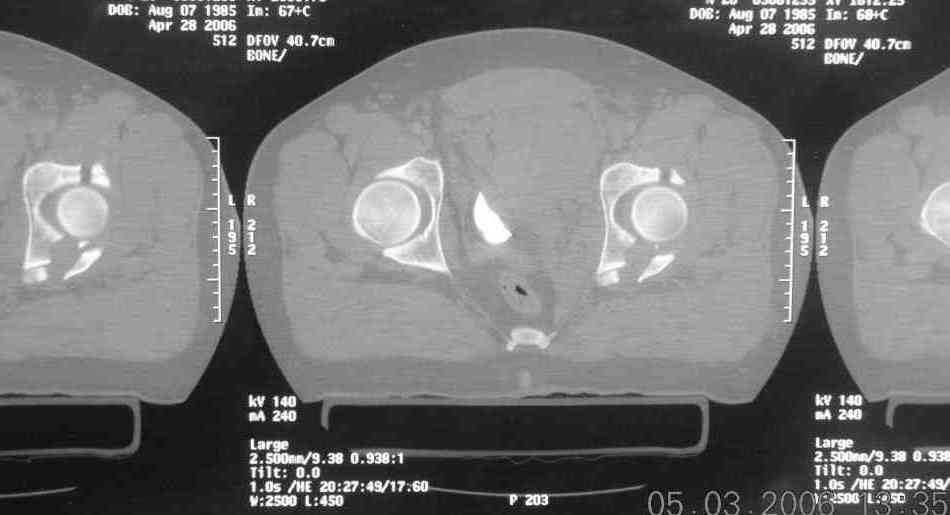

45 yo male in MVA, only other injury=small subarrachnoid bleed (neurologically fine, GCS never <14), with this transverse & associated posterior wall fx-dislocation 7/7

Biggest problem appears to be impaction & comminution of the posterior wall fx site - you've left out some CT cuts. This is not just fragments in joint. It may leave a deficient area, &/or block satisfactory posterior wall reduction.

The 2nd example is of a motorcyclist with a transverse fracture-dislocation...he had a closed attempted reduction and placed in traction but the manipulative reduction was not concentric (not unusual for this injury pattern)...so the traction was adjusted to be just enough to disengage the head from the fracture (12#) until he could be cleared for surgery one day after injury...he was treated "urgently" then with a prone KL, clean the fracture, reduce and clamp it, screw it, support with a balanced plate, close, and enjoy...2-3hours, 400cc EBL, blah, blah, blah..